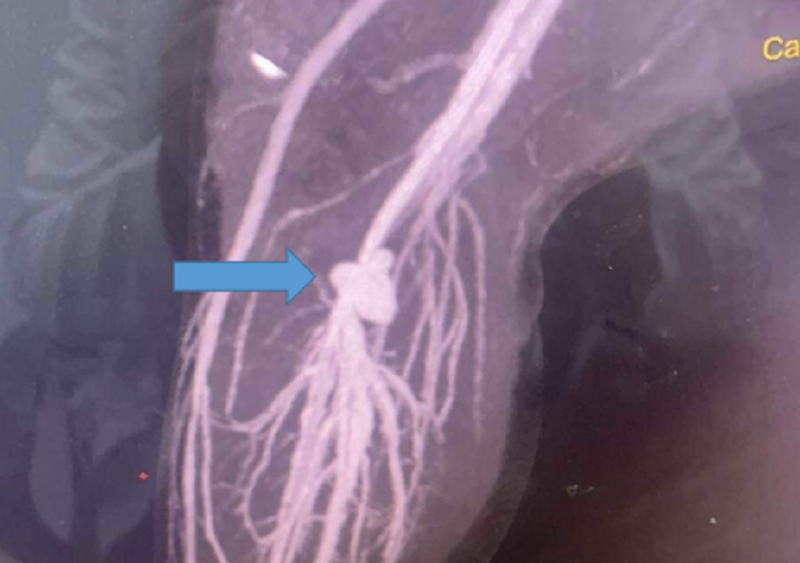

| Vị trí động mạch bị rách tạo thành túi phình khiến bệnh nhi đau đớn dữ dội (ảnh: BSCC) |

Tuy nhiên, 4 ngày sau, chân của bệnh nhi sưng lớn, tình trạng đau nhức ngày càng dữ dội. Gia đình đã chuyển trẻ đến Bệnh viện Nhi đồng Thành phố điều trị. Tại đây, kết quả chụp CT-Scan mạch máu cản quang ghi nhận, bé bị tắc đoạn cuối tĩnh mạch khoeo tại vị trí túi phình.

Các bác sĩ đã quyết định phẫu thuật mở rộng vết thương bóc tách cơ, bộc lộ tìm hệ thống mạch máu vùng khoeo chân trái. Quá trình phẫu thuật ghi nhận vị trí tổn thương do kéo đâm đã gây rách động mạch khoeo chân trái, tạo túi phình mạch máu thông thương với tĩnh mạch đã bị đứt gần như hoàn toàn.